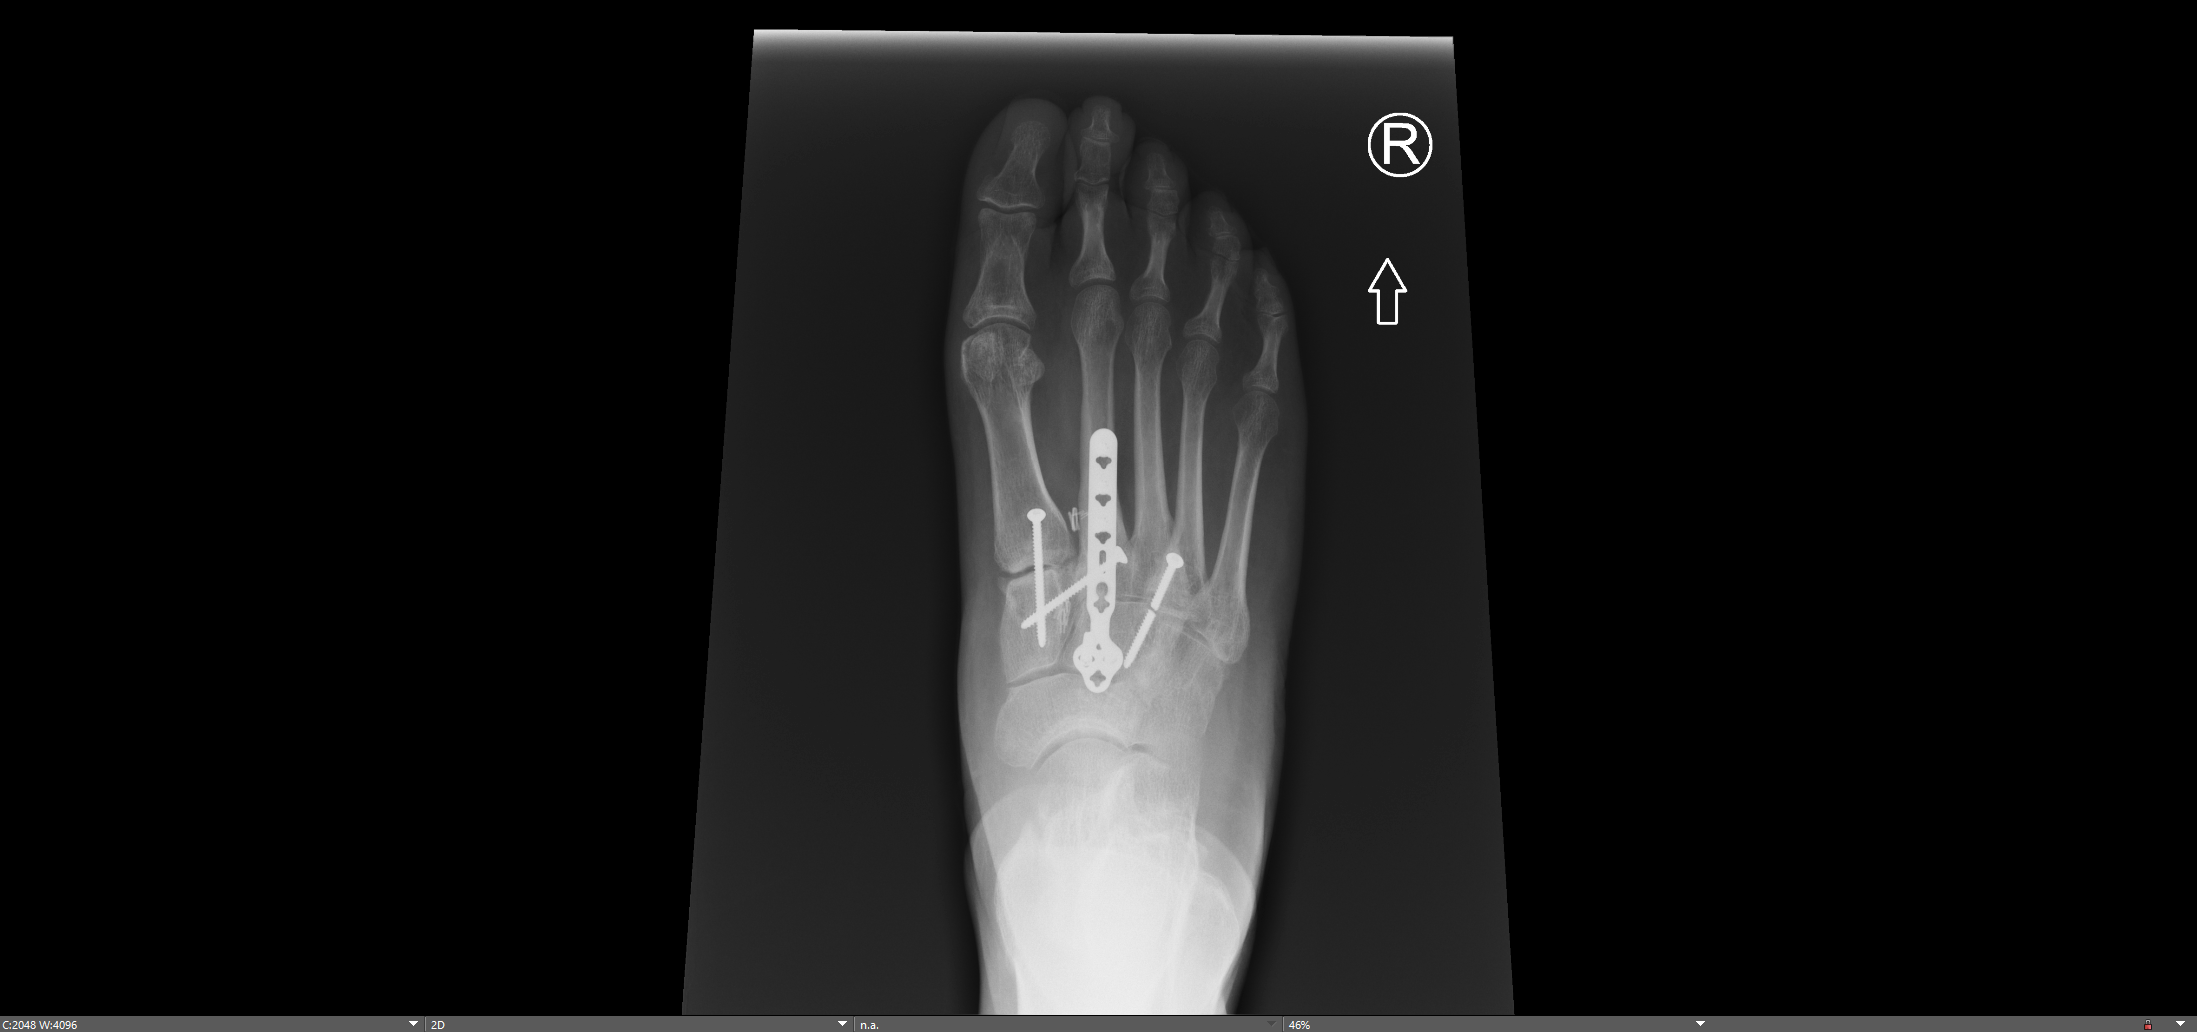

Midfoot fusion after LisFranc ORIF (Revision Surgery)

Post-operative xrays demonstrating removal of previous hardware and solid fusion across the 1st, 2nd, & 3rd TMT joints